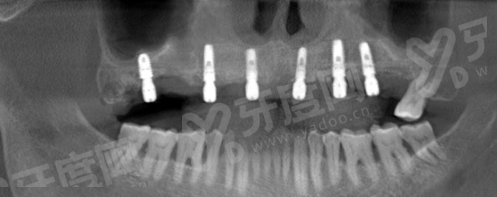

1、工欲善其事,必先利其器。广州中家医家庭医生口腔口腔部 (荔湾院区) 紧跟国内外前列技术,引进了精良的数字化口腔扫描及导航种植系统。这套系统就像给医生装上了“透视眼”和“导航仪”,能在术前严谨模拟种植位置、角度和深度。

2、得益于数字化技术的辅助,医院能够实现真正的微创种植。手术切口小、出血少、术后肿胀轻,大大缩短了患者的修复期。对于害怕看牙、担心疼痛的中老年朋友来说,这种舒适化的治疗体验无疑是一个巨大的福音。yadoo.cn

3、此外,医院还支持即刻种植、即刻负重等精良术式。这意味着部分符合条件的患者在拔牙后可以立即植入种植体,甚至当天就能戴上临时牙冠,修复了咀嚼功能,极大地缩短了缺牙等待期。这种效率高、精细的技术实力,充分证明了广州中家医家庭医生口腔口腔部 (荔湾院区) 种植牙靠谱么这个问题的肯定答案。